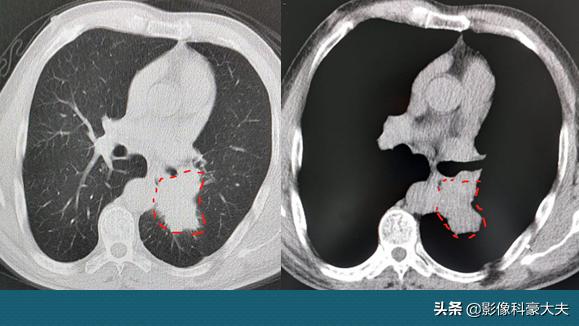

2.中心型肺癌,有点大,全肺切除

这位老爷子64岁,咳嗽咳痰40天,加重4天,CT发现左侧中心型肺癌,支气管镜病理为中分化鳞癌。病灶侵犯肺门血管(未侵犯心包内段,尚有手术条件),做了左肺全切,到下个月就3年了,近期复查没有复发:

2年半后

中心型肺癌的手术难度,常常比周围型更大,尽量去上级医院看看,准确判断有无手术机会,有时候需要PET-CT做整体评估,有点贵,但精准的术前分期往往能让更多病人获益。